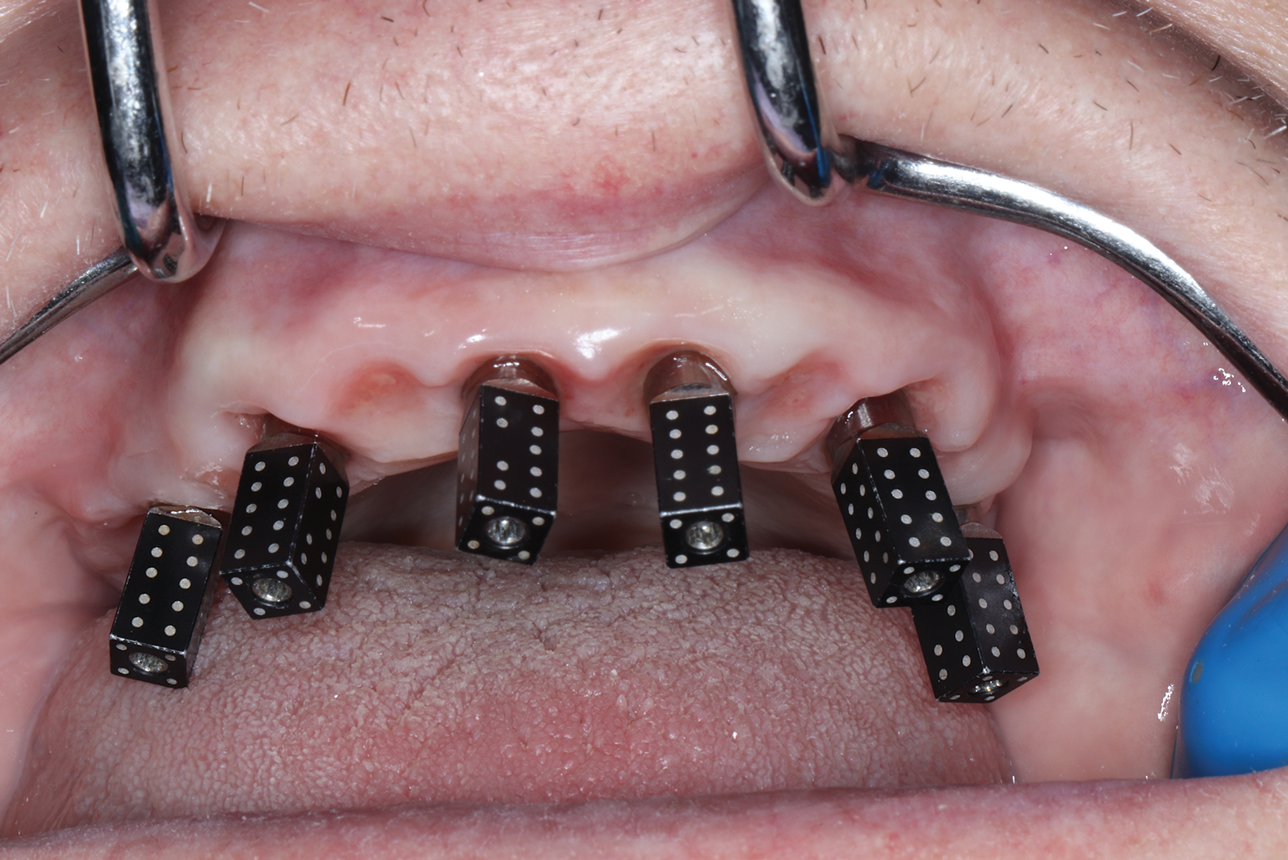

(8.) Photogrammetry scan body “dominos” inserted intraorally and ready for capture.

Figure 8

(9.) Photogrammetry uses a light source from an extraoral optical scanner applied intraorally to capture the scan bodies.

Figure 9

(10.) Scan bodies captured by photogrammetry that are ready for exportation to CAD software.

Figure 10

Overcoming the obstacle of stitching together images with overlapping scan bodies and tissue has long impeded the accuracy of intraoral full-arch implant capture. However, a successful solution has been developed using dental photogrammetry systems (eg, iMetric iCam4D, Voxel Dental; PIC System, PIC Dental; MicronMapper, SIN 360). Photogrammetry involves attaching implant markers (ie, scan bodies, scan flags) to multi-unit abutments and then capturing multiple images from various angles using an extraoral optical scanner (Figure 8 through Figure 10).8 These images are then input into CAD software, matched to intraoral scans, and processed to create highly accurate virtual 3D models of arches and their surrounding structures. After inputting the data, technicians can seamlessly design tooth setups using a fully digital workflow.